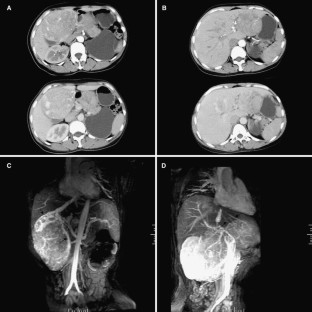

Fig. 2